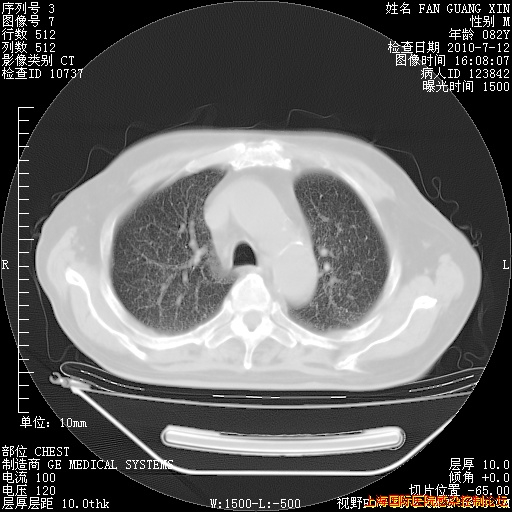

今天复查CT

今天CT

整整相隔30天的肺部CT好像有所好转啊。甲强龙减量第3天,需要观察体温。

海管,自昨日你和我通完话后,不知您岳父消化道症状有无缓解?体温怎样?阅读7.12日胸部ct,个人认为目前激素治疗是有效的,甲强龙减量是适宜的。因在抗痨治疗,需密切观察肝功、肾功能和血常规。不过,老年、长期住院和大量使用激素,很担心菌群失调发生